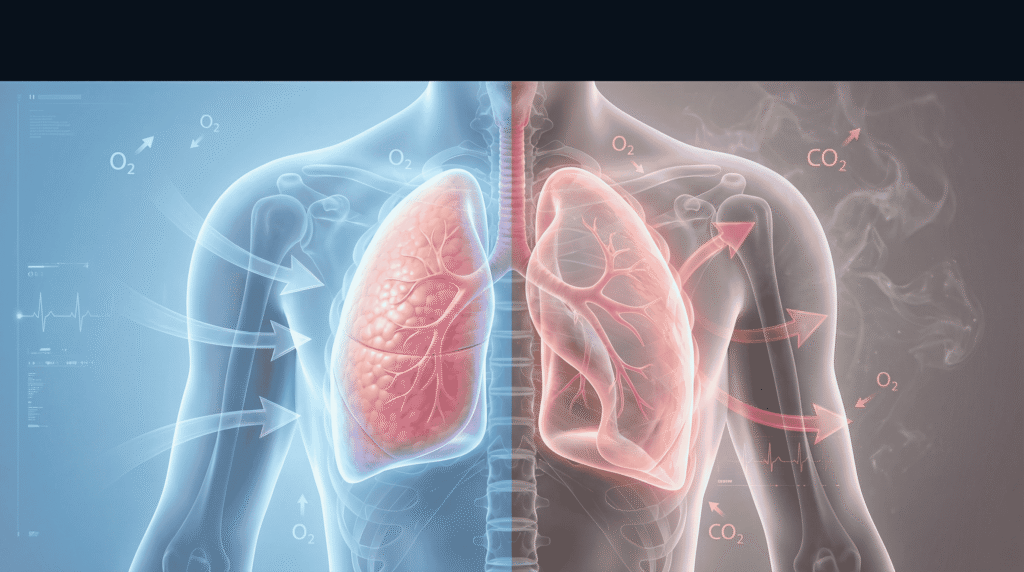

2. क्या अंदर ली गई हवा और बाहर निकली हवा हमेशा बराबर होती है?

हाँ, लगभग बिल्कुल बराबर!

लंबे समय में फेफड़ों का आकार स्थिर रहता है, इसलिए जितनी हवा अंदर जाती है, उतनी ही बाहर आती है।

(वैसे थोड़ा-सा वैज्ञानिक अंतर होता है – हवा गर्म होने और गैस एक्सचेंज की वजह से बाहर की हवा का वॉल्यूम कुछ मिलीलीटर ज्यादा हो सकता है, लेकिन हम इसे नजरअंदाज करके बराबर मानते हैं।)

- खून में CO₂ बढ़ना (Hypercapnia)

- ऑक्सीजन की कमी (Hypoxemia)